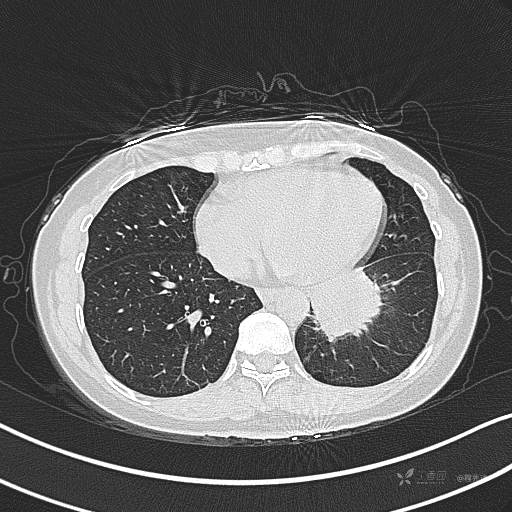

CT平扫

肺窗